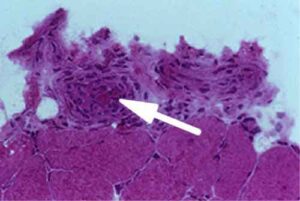

“La risoluzione d’immagine – ha spiegato Ardigo’ – e’ sovrapponibile a quella della microscopia ottica standard e permette di ottenere informazioni analoghe senza dover sottoporre il paziente a dolorose biopsie cutanee, che oltretutto lasciano cicatrici. Grazie alla assoluta non invasivita’, l’indagine puo’ essere ripetuta su piu’ lesioni cutanee nella stessa seduta e piu’ volte nel tempo, al fine di controllare i cambiamenti microscopici e valutare l’efficacia delle terapie adottate”. I primissimi lavori di ricerca sulla microscopia confocale risalgono alla meta’ degli anni Novanta al Wellman Institute di Harward. Agli inizi del 2000, Salvador Gomzalez, docente allo stesso istituto, avvia le prime applicazioni su paziente. Si formano gruppi di lavoro, prevalentemente a New e a Boston, e, in Italia, a Modena e a Roma, e per ultimo a Berlino. Ma e’ al San Gallicano che Ardigo’ sviluppa le applicazioni cliniche piu’ avanzate nello studio delle malattie infiammatorie, che hanno richiamato l’attenzione della comunita’ scientifica internazionale.